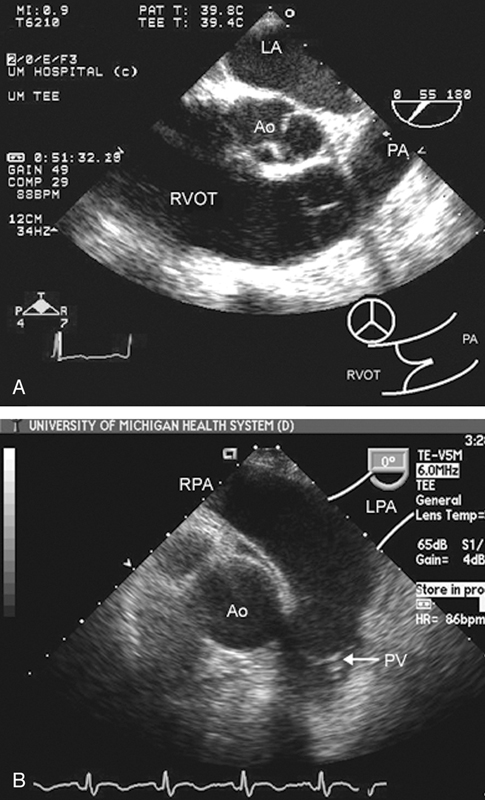

فحوصات تشخيصية لبعض امراض القلب والشرايين التاجية